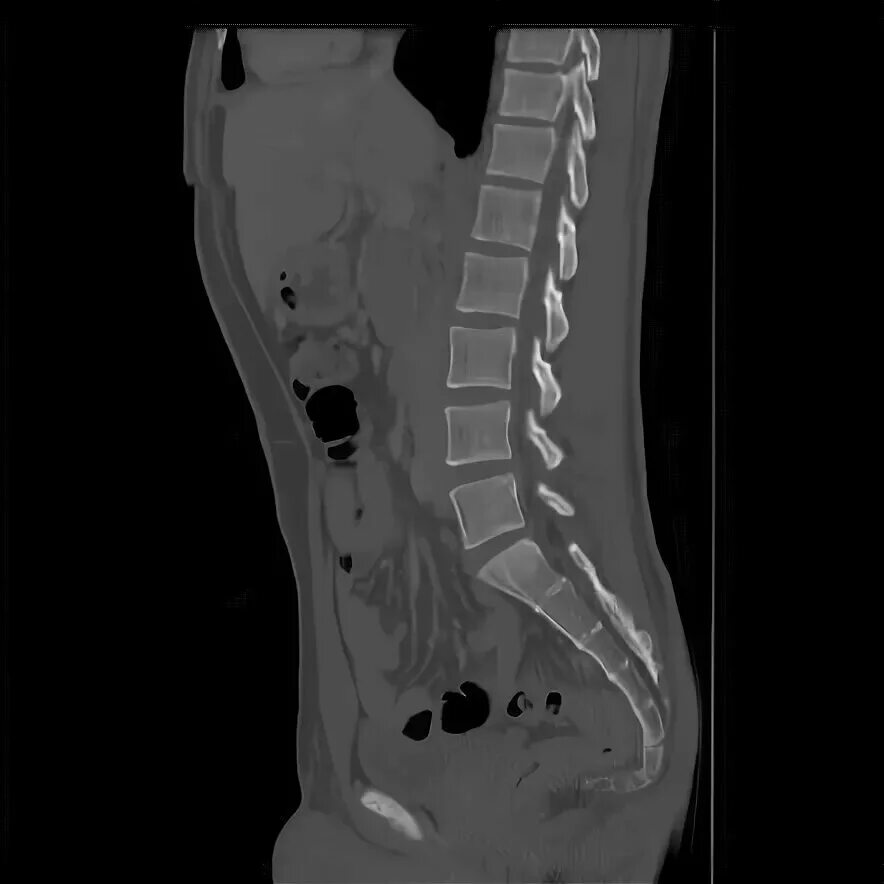

Копчик вверх